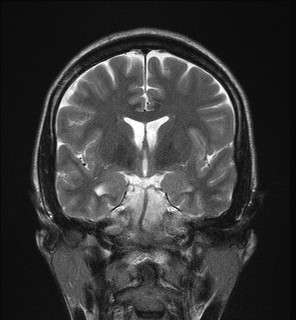

Hippocampal sclerosis (HS) is a neuropathological condition with severe neuronal cell loss and gliosis in the hippocampus, specifically in the CA-1 (Cornu Ammonis area 1) and subiculum of the hippocampus. It was first described in 1880 by Wilhelm Sommer.[1] Hippocampal sclerosis is a frequent pathologic finding in community-based dementia. Hippocampal sclerosis can be detected with autopsy or MRI. Individuals with hippocampal sclerosis have similar initial symptoms and rates of dementia progression to those with Alzheimer's disease (AD) and therefore are frequently misclassified as having Alzheimer's Disease. But clinical and pathologic findings suggest that hippocampal sclerosis has characteristics of a progressive disorder although the underlying cause remains elusive.[2] A diagnosis of hippocampal sclerosis has a significant effect on the life of patients because of the notable mortality, morbidity and social impact related to epilepsy, as well as side effects associated with antiepileptic treatments.[3]

Mesial temporal sclerosis is a specific pattern of hippocampal neuron cell loss.[4][5] There are 3 specific patterns of cell loss. Cell loss might involve sectors CA1 and CA4, CA4 alone, or CA1 to CA4.[5] Associated hippocampal atrophy and gliosis is common.[4] MRI scan commonly displays increased T2 signal and hippocampal atrophy.[4] Mesial temporal sclerosis might occur with other temporal lobe abnormalities (dual pathology).[4] Mesial temporal sclerosis is the most common pathological abnormality in temporal lobe epilepsy.[4][5] It has been linked to abnormalities in TDP-43.[6]